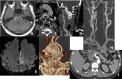

Fig. (14)

In a patient with thromboembolic infarction within right cerebellum (A), CTA (B, C, D) shows normal caliber of left VA at the proximal part of the V3 and V4 but narrowed at the distal part of the V3 (short arrow showing distal V3 on C) (long arrows showing proximal V3 and V4 on D). Distal V3 narrowing (C) is associated with intramural hematoma (crescent sign) on fat sat T1W images (E). Findings are suggestive of distal V3 dissection.